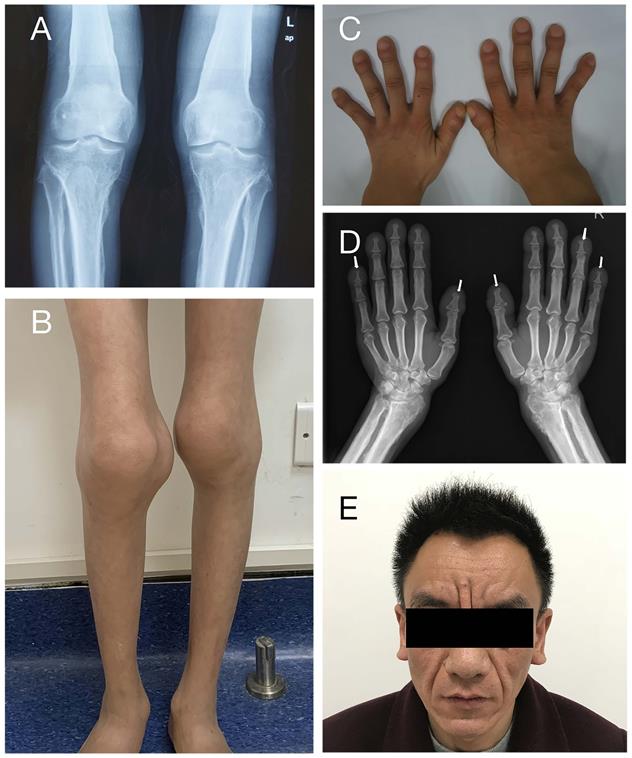

A total of 12 patients from 11 families were enrolled in this study, including eleven males and one female, with a median onset age of 2.0 years (range: 1.0-18.0 years). Table 1 summarizes the patients' clinical characteristics. The initial symptom of all patients is digital clubbing, which always occurs in infancy or early childhood. Digital clubbing and periostosis are the most frequent characteristics as they were presented in all patients. The degrees of digital clubbing are listed in Table 1, and more than half patients presented with severe digital clubbing. As for skin manifestations, eight patients have pachydermia and most of them were with a mild degree. Only patient 9 characterizes with severe pachydermia (Figure 2E). Ten patients (83.3%) had joint swelling and four of them (33.3%) were accompanied by arthralgia. The knee joint is most often involved, as all ten individuals complained about knee joint swelling, followed by ankles (seven patients) and wrist (one patient). Patient 10 and patient 12 were found to have patent ductus arteriosus (PDA) at birth. It closed spontaneously in patient 10 at the age of four without any treatment. Patient 12 took surgery and recovered. The incidences of other clinical features are listed in Table 1. None of our patients presented with hypoalbuminemia or gastrointestinal hemorrhage.

Clinical features of PHOAR1 patients. (A) Periostosis in knee joints (Patient 3). (B) Joint swelling (Patient 11). (C) Digital clubbing (Patient 3). (D) Acro-osteolysis (Patient 9). (E) Severe facial pachydermia (Patient 9).